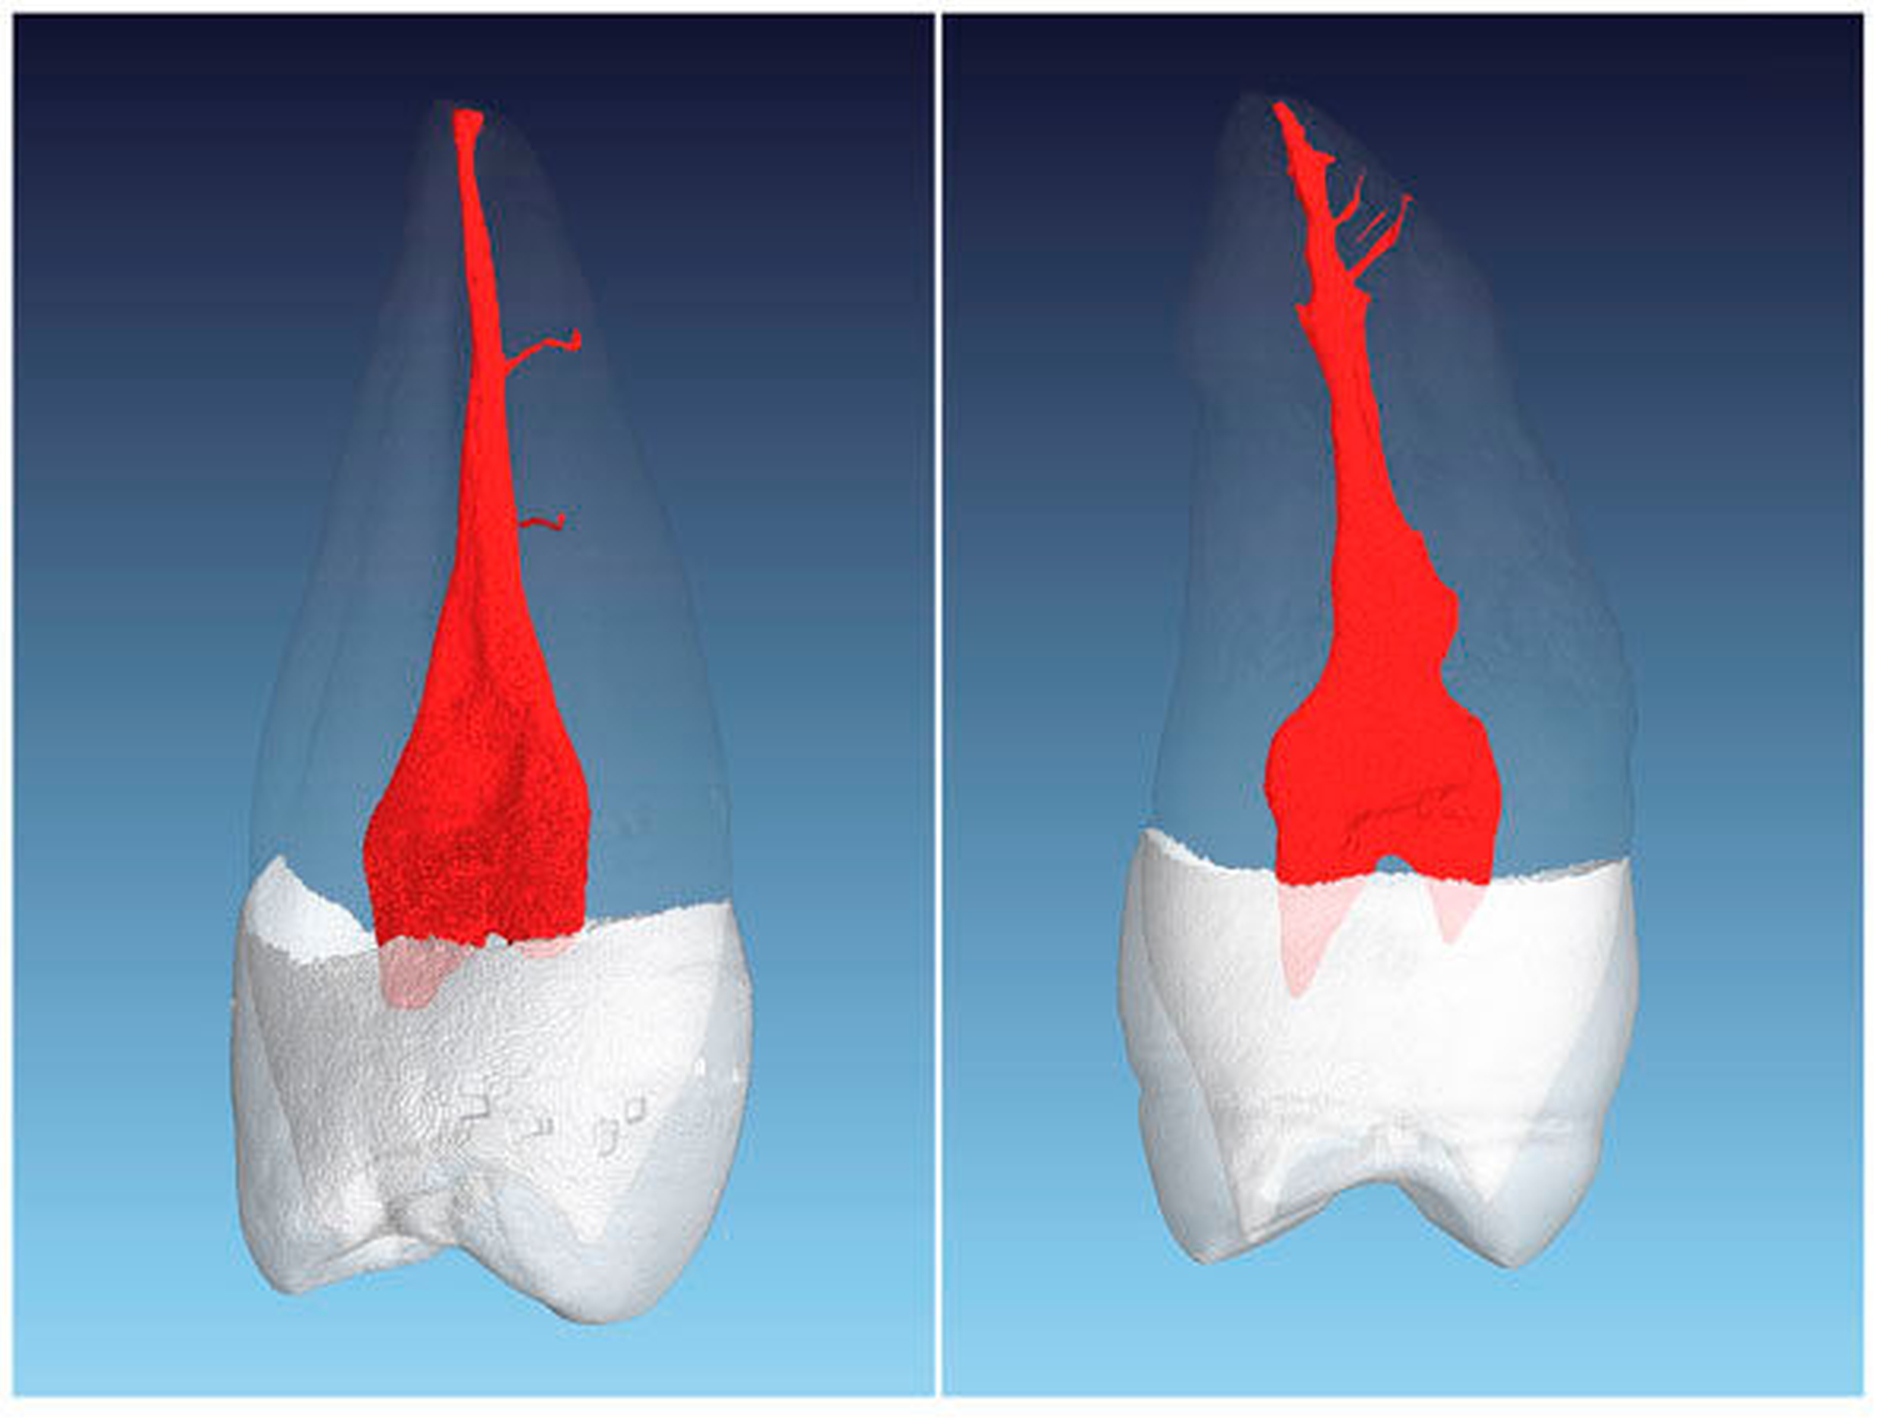

Beide Prämolaren können drei Kanalsysteme mit drei Wurzeln oder drei Kanalsysteme mit zwei beziehungsweise mit einer Wurzel aufweisen (Abbildung 7). Das Auftreten dieser Kanalkonfigurationen wird in der Literatur mit 1 bis 2 Prozent beschrieben [Sert und Bayirli, 2004].

Drei mögliche Hinweise können bei der Diagnostik eines dreikanaligen Prämolaren hilfreich sein. Der erste Hinweis ist eine nicht klar abzugrenzende Wurzelkontur in der diagnostischen Röntgenaufnahme. Dreikanalige obere Prämolaren zeigen im klassischen Röntgenbild im koronalen bis mittleren Wurzeldrittel eine oft bauchige Struktur. Diese korrespondiert in der Regel mit der Stelle apikal der Aufteilung in zwei bukkale Kanäle (Abbildung 8). Klinisch kann dann in den meisten Fällen bei Sondierung bukkal eine deutliche Einziehung unterhalb der Schmelz-Zement-Grenze mit der Sonde ertastet werden, dies ist der zweite Hinweis (Abbildung 9). Der dritte Hinweis zeigt sich nach Trepanation und Darstellung des Kavumbodens und des vermeintlichen bukkalen Kanaleingangs. Dieser wird häufig nach hinreichender Darstellung in mesiodistaler Richtung oval und gibt dann die Sicht auf die beiden eigentlichen Kanäle frei (Abbildungen 10 und 11).